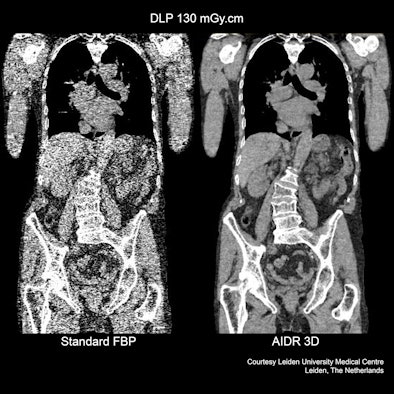

| Comparison of Toshiba's AIDR 3D and conventional filtered back projection view of the torso. |

Manufacturers of CT technology face a continuous challenge in setting themselves ever more stringent targets for reducing exposure to potentially harmful radiation. At ECR 2012, Toshiba Medical Systems Europe is introducing two new series of CT scanners incorporating its latest dose reduction technology, AIDR 3D. This Adaptive Iterative Dose Reduction software will be a standard feature on its RXL series, and will be available in a 16 and 32 slice configuration. On its CXL series, it will be available in a 64 and 128 slice configuration. The company has also announced a comprehensive upgrade scheme covering the entire European installed base of Aquilion One, Premium and Prime scanners.

Iterative-based dose reduction software requires extensive computational power, which often results in much longer reconstruction times that limit its clinical usage, especially in those examinations requiring a fast diagnosis. However, the company believes that through a combination of powerful hardware and its new AIDR 3D software its new technology will greatly extend the clinical utility of this approach.

"AIDR 3D is fully integrated in scan protocols for improved workflow, assuring a dose reduction in a clinical setting by up to 75%," noted Henk Zomer, CT business unit manager for Toshiba in Europe. "It offers a substantial noise reduction and improved spatial resolution. We also believe that this is unique software in that produces minimal penalties in reconstruction times, while assuring the best diagnostic image quality at the lowest dose for all patients. AIDR 3D works both in the image and raw data domain and is fully integrated in the exposure control for optimized dose control in all clinical settings, even in emergency departments."

The new system aims to provide benefits in terms of its diagnostic performance, which Toshiba plans to demonstrate at is exhibition stand. Since the software is adaptive, special operator handling is not needed. Automatically optimized iterations assure best image quality for each particular body region, according to Zomer.